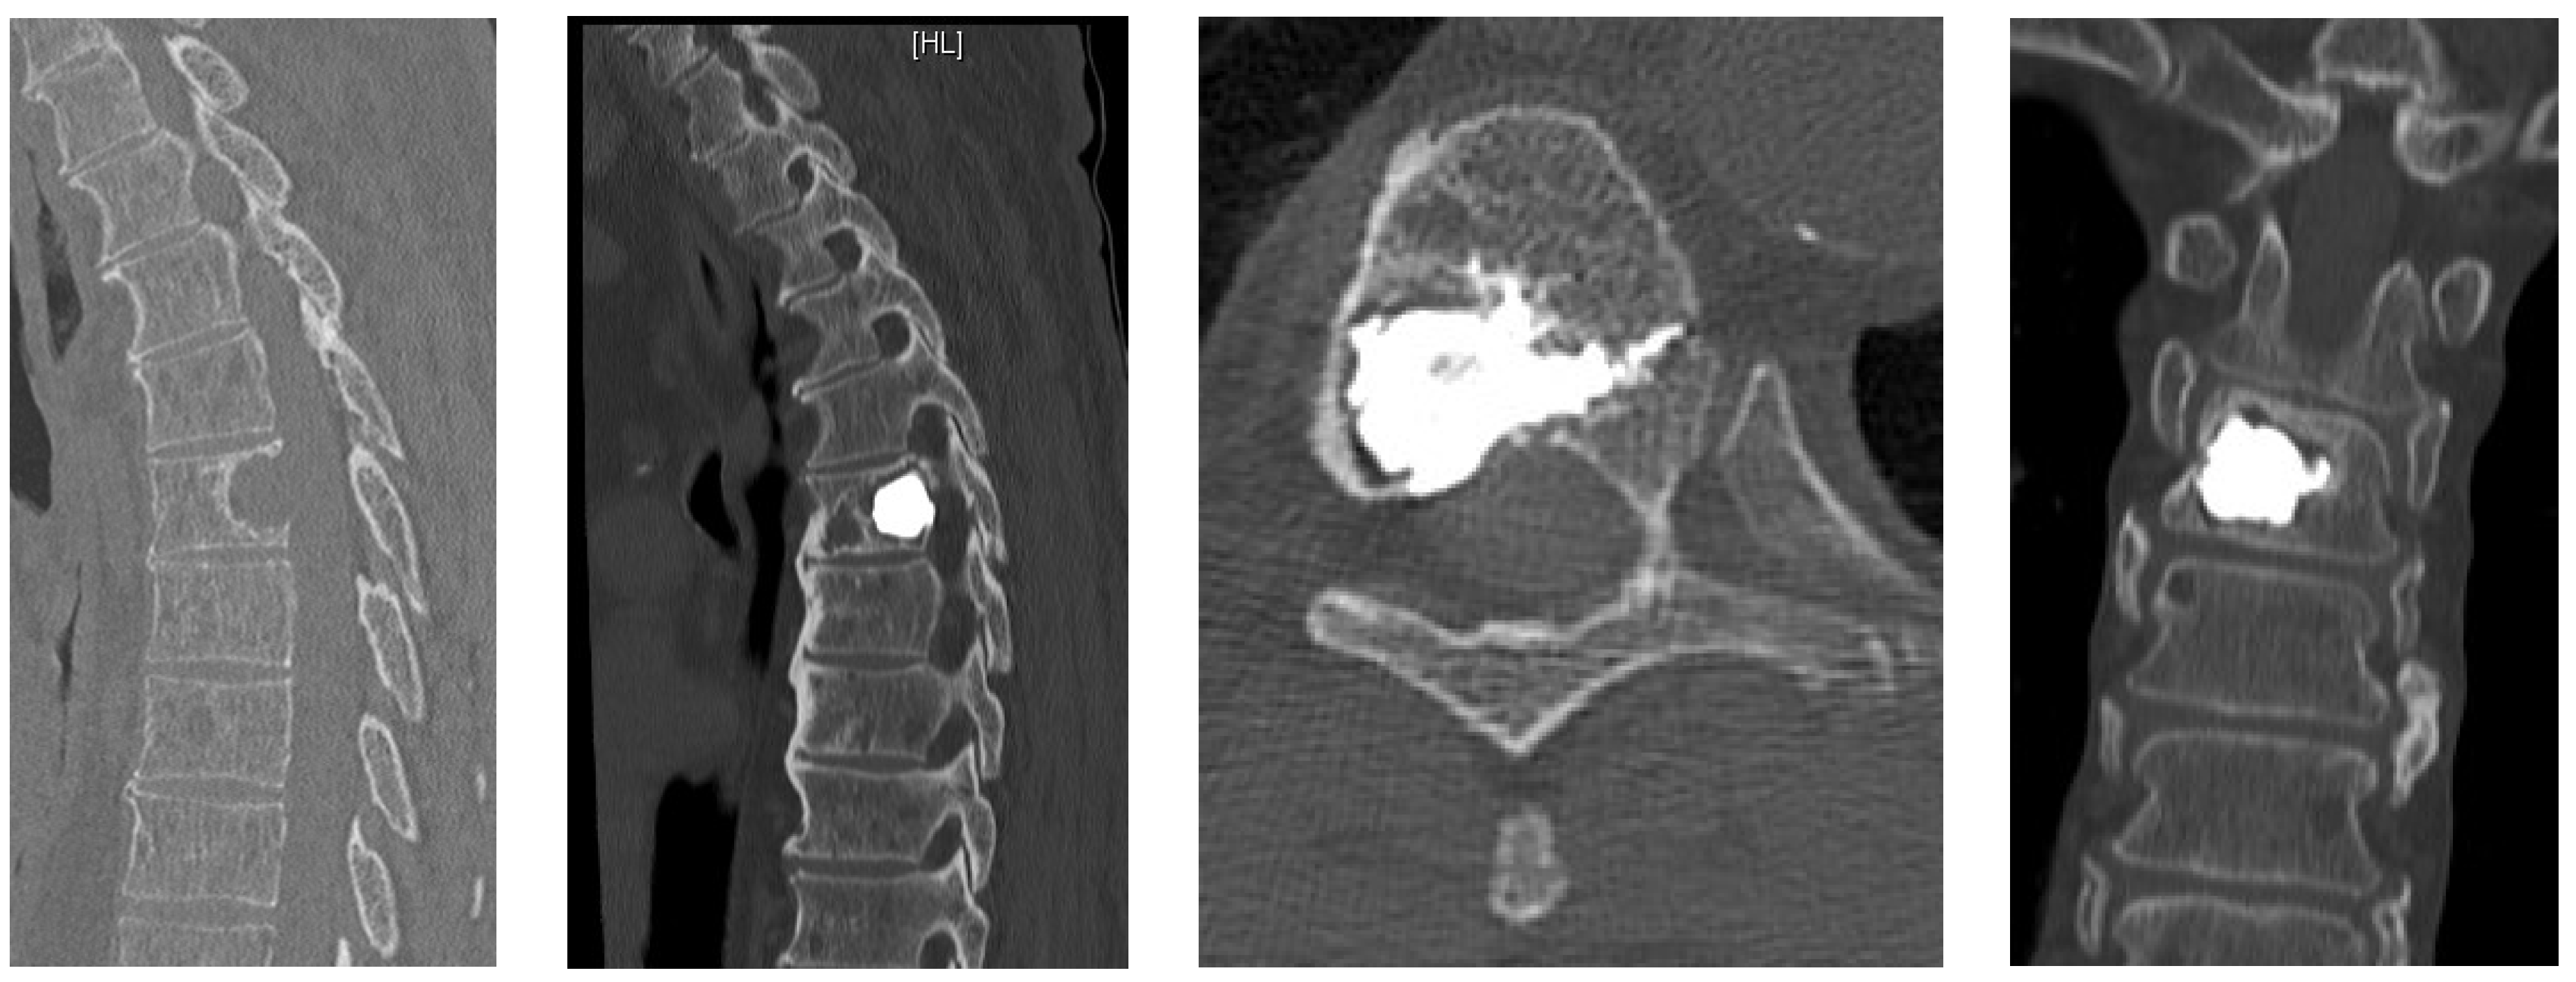

- Unrestricted reconstruction of datasets with views along the path of the needle with planning in 3D and 2D reconstructions (Figure 1).